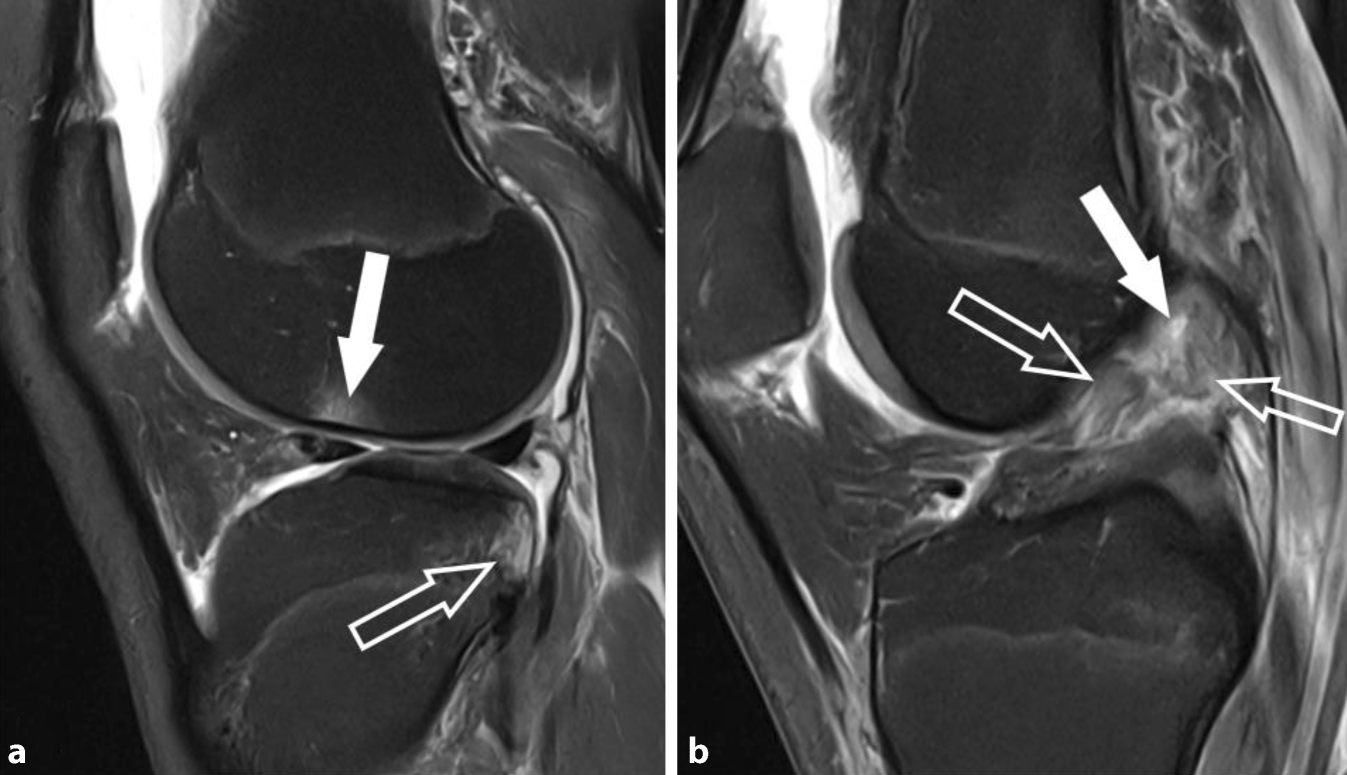

Abb. 2

MRT des Kniegelenks einer 17-jährigen Fußballspielerin nach Kniedistorsion mit sagittalen protonendichtegewichteten (PD) Schichten mit Fettsuppression. a Schnitt durch das laterale Kniekompartiment mit Darstellung von fokalen Knochenmarködemen der lateralen Femurkondyle auf Höhe des kondylopatellaren Sulkus (weißer Pfeil) und am posterolateralen Tibiaplateau (hohler Pfeil), welche typisch für Kontusionsödeme im Rahmen eines Pivot-shift-Mechanismus sind. b Schnitt durch das zentrale Kniegelenk mit Darstellung einer vollständigen Ruptur des vorderen Kreuzbands (VKB) im proximalen Anteil mit Nachweis von rupturierten Fasern und Spaltbildungen (weißer Pfeil). Die ödematösen VKB-Fasern sind gewellt und abweichend von der Blumensaat-Linie orientiert, was sichere Zeichen einer VKB-Ruptur sind